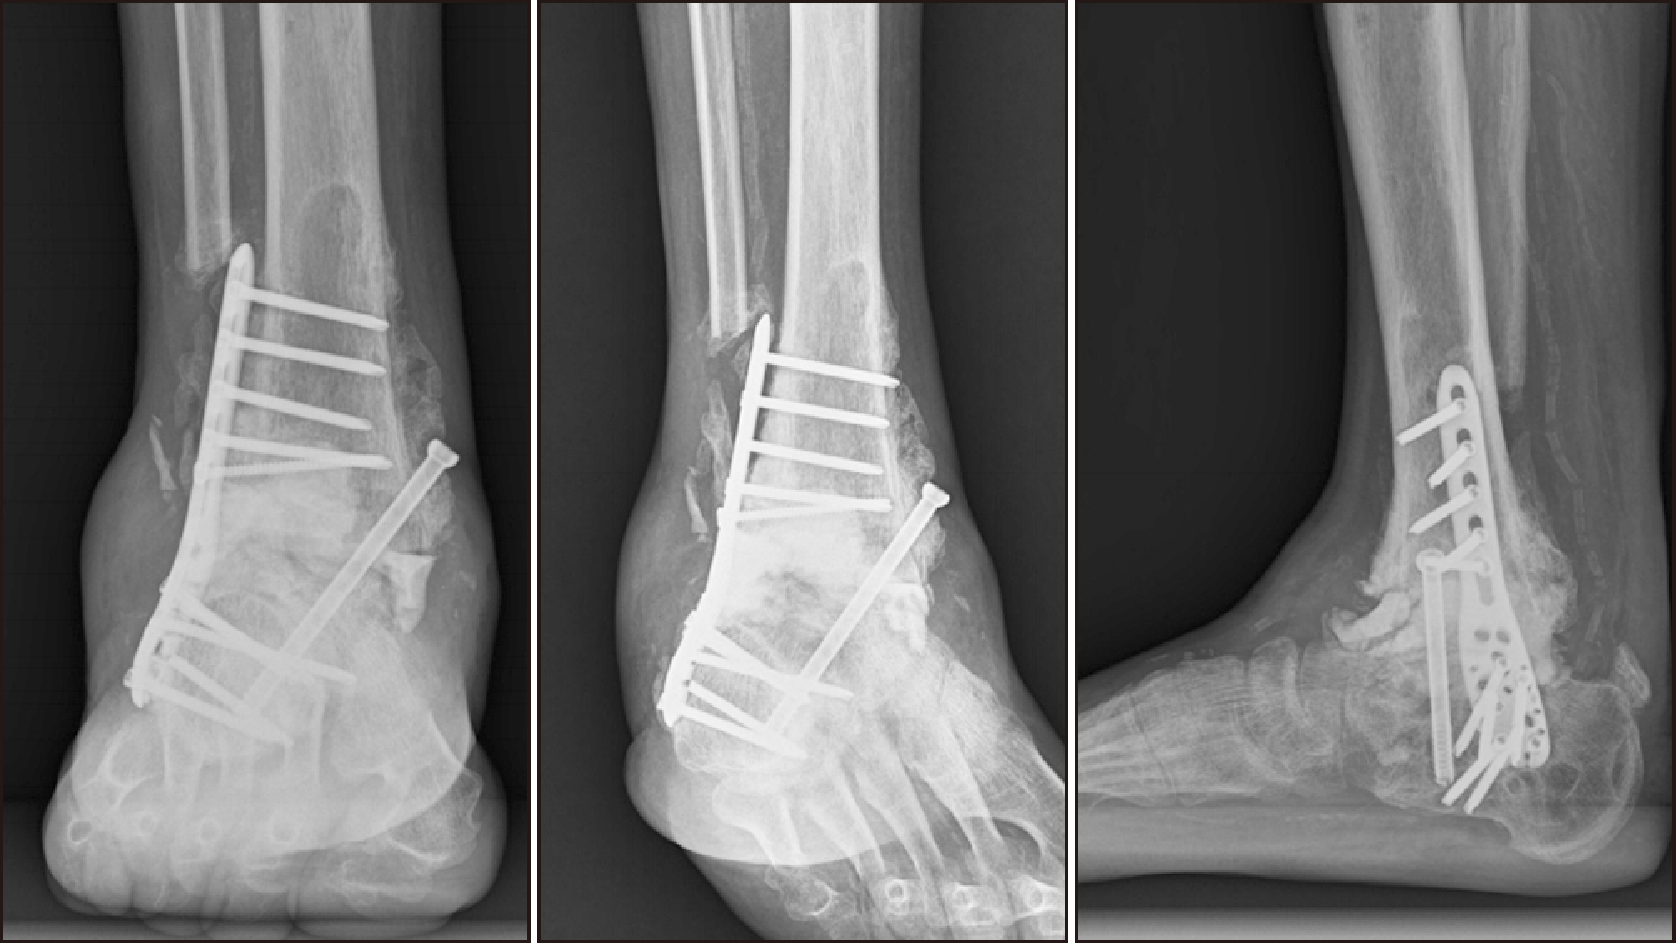

After the stabilization of the acute symptoms, the patient underwent OR/IF. A plate and screws were utilized for the lateral malleolus and K-wires were employed for the medial malleolus. In addition, syndesmotic fixation was performed to stabilize the distal tibiofibular joint (Fig. 3). In this case, K-wire was used for syndesmotic fixation due to the poor soft tissue condition observed around the medial malleolus. While screw fixation or suture anchor may provide stronger stability, the less invasive nature of K-wire was prioritized to minimize additional injury. Additionally, given the risk of poor bone quality we sought to avoid hardware failure or excessive stress. Upon observing a reduction in post-operative swelling, a short leg cast was applied (Fig. 4).

Figure 1

(A) Initial radiograph imaging upon admission showing a right ankle trimalleolar fracture. (B) Initial clinical picture upon admission showing a right ankle trimalleolar fracture.

Figure 4

Post-cast radiograph following the application of a short leg cast after the reduction of swelling.